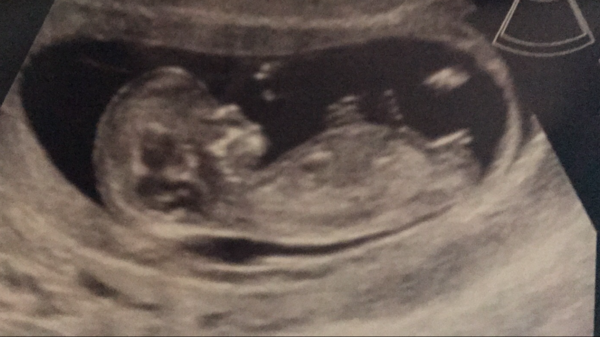

MrsGB2225 · 14/05/2017 11:13

Here's our little wriggler

Lovely scan MrsGB.